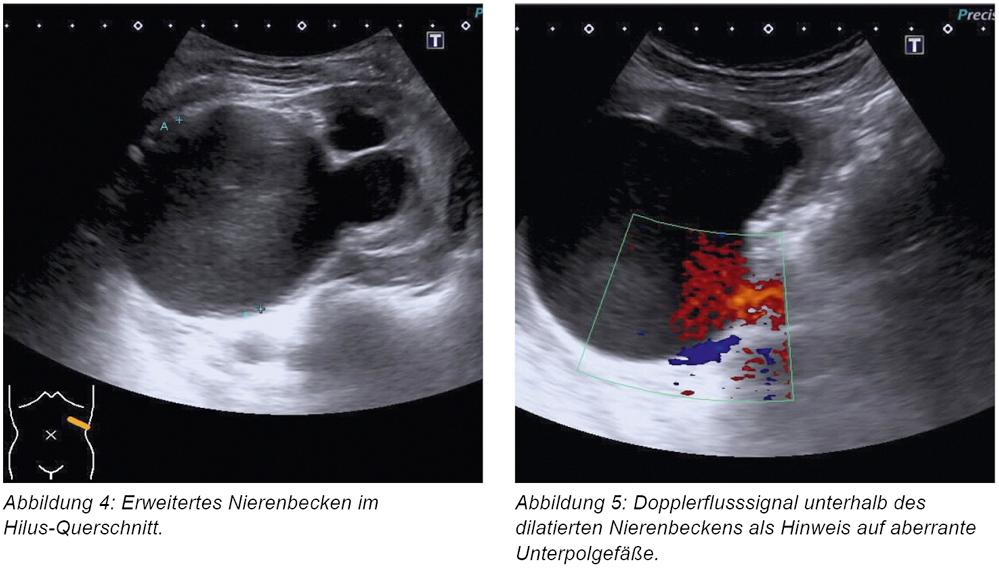

Die durchgeführte Abdomensonografie zeigte eine vergrößerte linke Niere mit verschmälertem Parenchymsaum. Ebenfalls zeigte sich linksseitig eine erhebliche Erweiterung des Nierenbeckenkelchsystems mit intra- und vor allem extra-renaler Nierenbeckenkelcherweiterung (extra-renaler Durchmesser von 65 mm) (Abbildung 4). Dopplersonografisch konnten aberrierende Unterpolgefäße identifiziert werden (Abbildung 5).

Zur erweiterten urologischen Diagnostik erfolgte eine dynamische Nierensequenzszintigrafie mit Tc 99m-MAG3 Clearance. Hierbei bestand eine ausgeglichene Nierenpartialfunktion mit obstruktivem Abflussmuster, auch nach Furosemid-Gabe (Abbildungen 6 und 7).

Unter Zusammenschau der bildgebenden Befunde ergab sich das Bild einer linksseitig dekompensierten Ureterabgangsstenose auf dem Boden aberrierender Unterpolgefäße. Unter analgetischer und spasmolytischer Behandlung waren die Schmerzen kontrollierbar. Ein begleitender Harnwegsinfekt wurde klinisch und laborchemisch ausgeschlossen. Therapeutisch führten wir eine zeitnahe operative Behandlung mittels Ureteropyeloplastik in minimalinvasiver Technik durch (Abbildung 8). Hierbei wurde unter Umgehung der akzessorischen Gefäße der stenotische Bereich des Harnleiters reseziert und ventral an das Nierenbecken reanastomosiert. Zur Sicherung des Harnabflusses wurde passager für sechs Wochen eine Harnleiterschiene eingebracht (Abbildung 9).